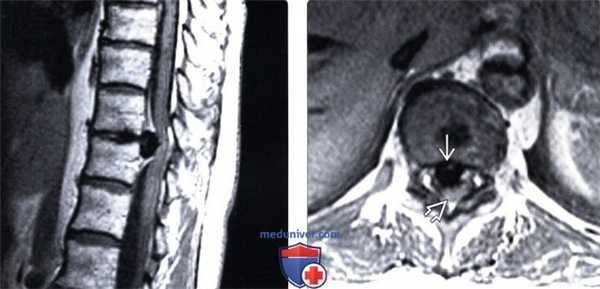

(Слева) Т2-ВИ, сагиттальный срез: языкообразная протрузия диска L4-L5. Наибольший краниокаудальный размер протрузии равен размеру ее основания, поэтому термин «протрузия» здесь следует считать наиболее подходящим.

(Справа) Т2-ВИ, аксиальная проекция: небольшая фокальная протрузия межпозвонкового диска L4-L5 справа, распространяющаяся в области выхода корешка L5. (Слева) Т1-ВИ, сагиттальный срез: крупная грыжа диска L3-L4, фрагмент которой мигрировал вниз до уровня 14 позвонка, что соответствует секвестрации диска (свободному фрагменту).

(Справа) Т1-ВИ, сагиттальный срез: фораминальная экструзия диска L4-L5, перекрывающая собой периневральную клетчатку. Имеет место импинджмент выходящего корешка L4.